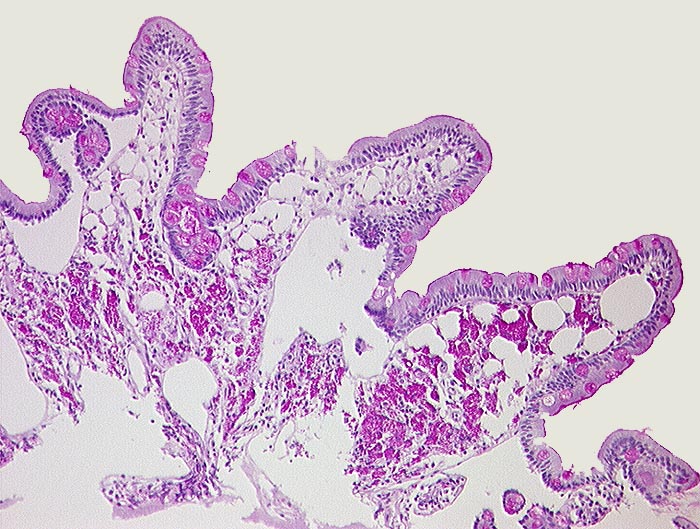

AP/ Morbus Whipple

Morbus Whipple

Entzündung infektiös

Dünndarm

Pathologischer Befund